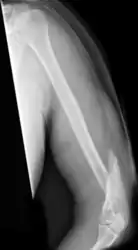

| Midshaft humerus fracture with callus formation | |